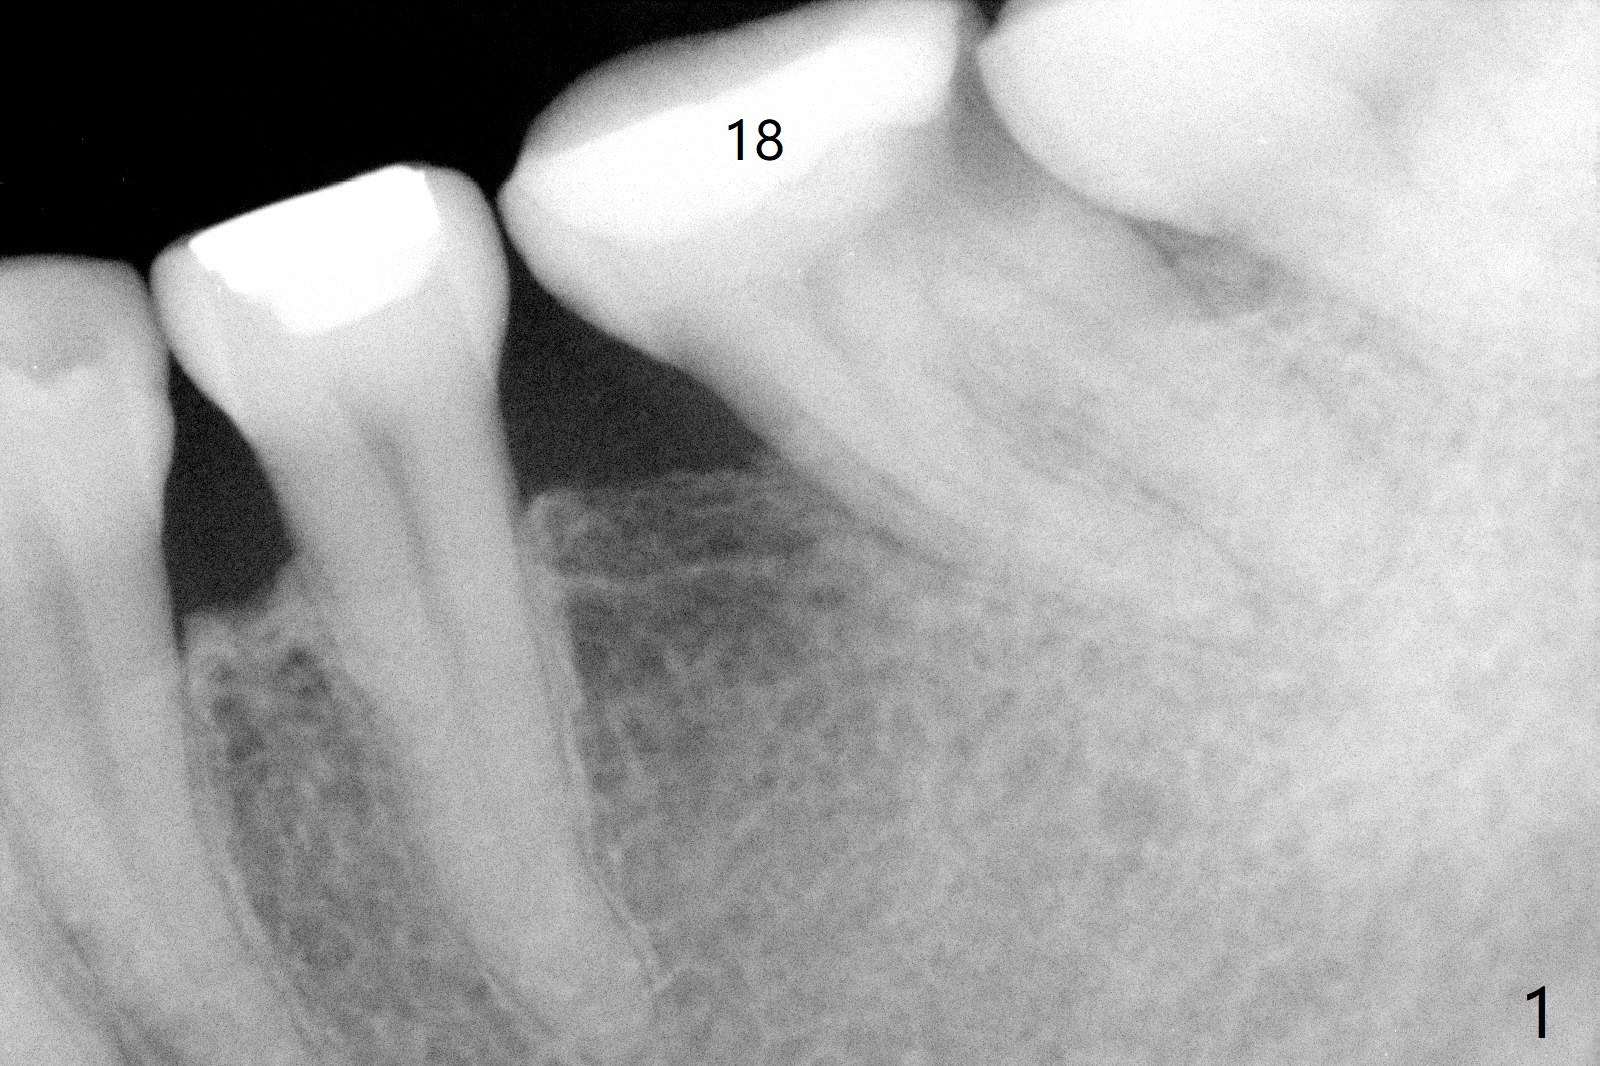

A 54-year-old woman, a dental phobic with RCT at #18 eight years ago (Fig.1,2), returns to clinic because of 2nd caries. New composite build-up is done around the old one before impression (Fig.3 N, O). BW will be taken before and after cementation for confirmation of marginal seal. How long will the crown of the tilted tooth last, as opposing to implants?